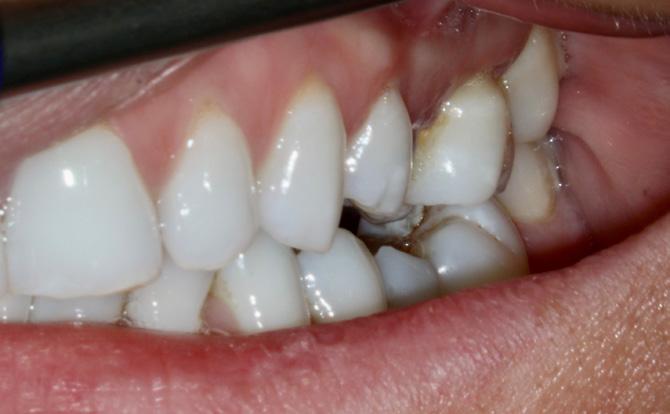

Case 2

Figure 7: Clinical photograph showing left posterior occlusal relationship.

Figure 8: Clinical photograph showing right posterior occlusal relationship.